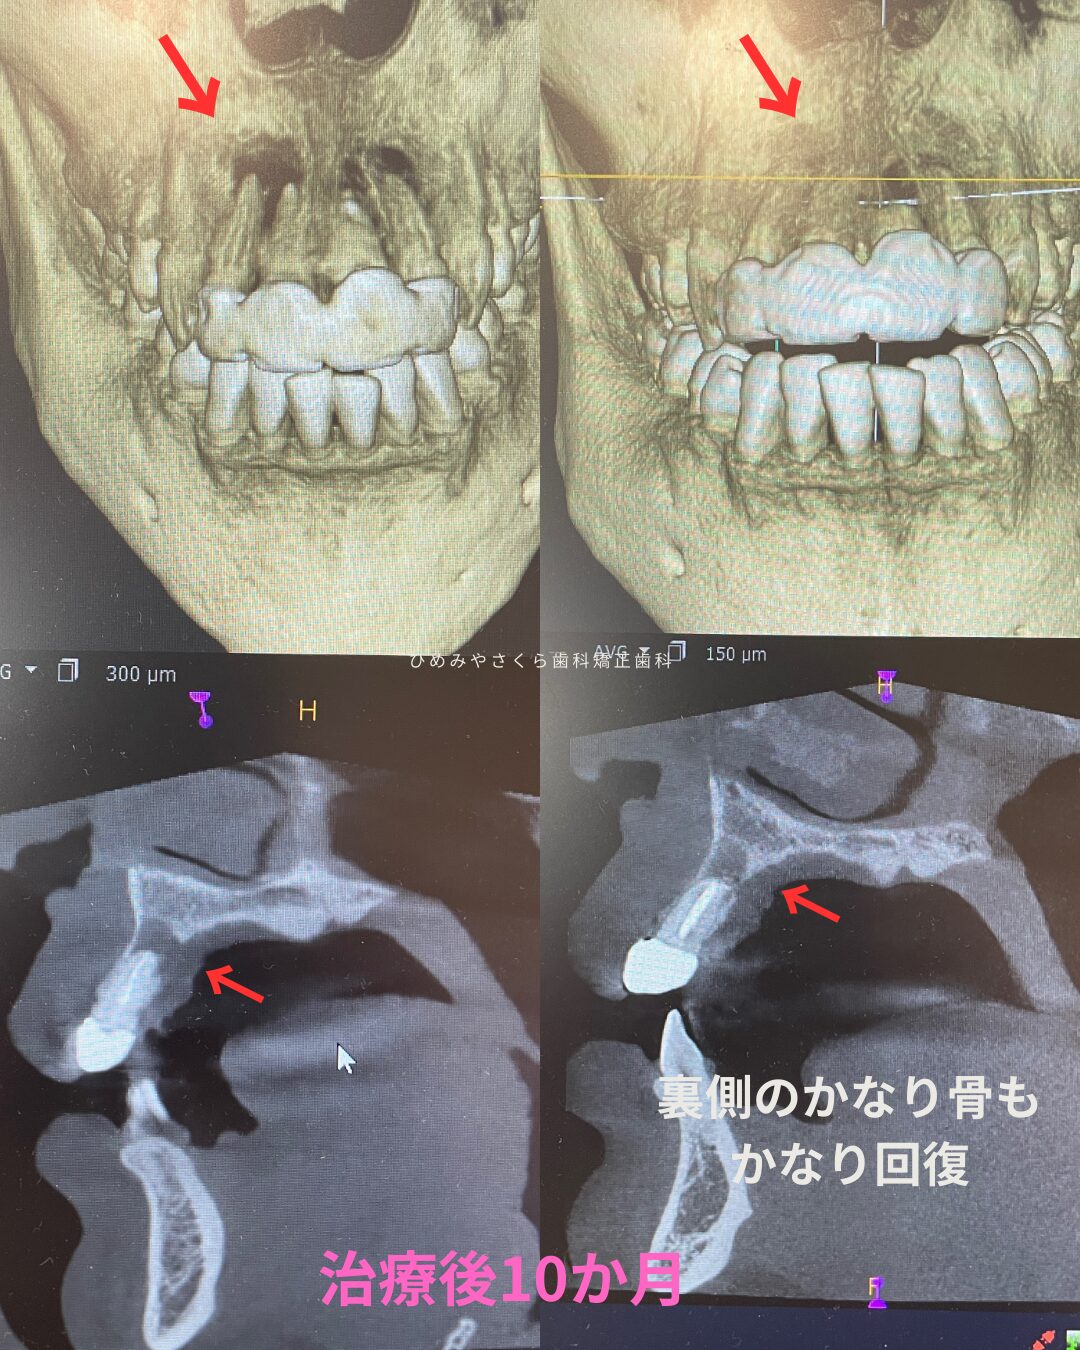

40代女性他院セラミックの修正治療

モニター様ご紹介 20年ほど前に他院で受けたセラミック治療をした歯のお痛みがあるのと、治した歯の周囲が黒く目立つので改善したいとご相談くださいました。当院に通ってくださっている方からのご紹介です。 初診時の状態 他院セラミックの上の歯茎が痛いという症状があったのでレントゲン撮影とCT撮影をしています。前歯の根の先に黒い影が見えます。これは根の先に膿が溜まって …